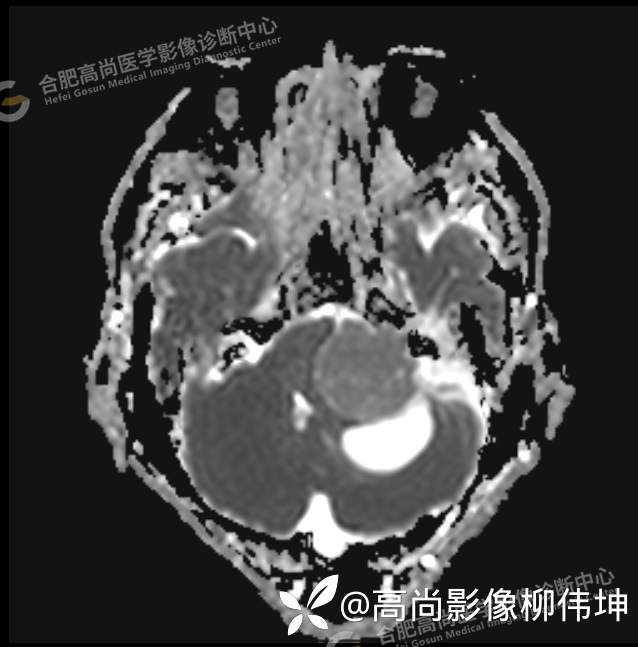

颅脑MRI平扫+增强示:双侧大脑半球对称,左侧桥小脑角区可见一团块状异常信号影,边界尚清,病灶与小脑幕宽基底附着呈“D”字征,上缘指状伸入幕缘上生长,病灶大小约43mmx42mmx36mm,其内信号不均,T1WI呈等低信号,T2WI呈混杂等高信号;FLAIR呈高信号,内可见条状低信号影,DWI呈稍高信号,ADC呈低信号,弥散轻度受限,病灶后方左侧小脑半球区可见一大小约33mmx16mm的弧形长T1长T2信号影,FLAIR呈低信号,其周围可见片状高信号影,相邻桥小脑角增宽。脑桥、小脑蚓部,小脑半球、第四脑室、环池受压变形,向右侧偏移,四脑室明显变窄,增强扫描病灶可见不均匀明显强化,邻近脑膜可见线样强化改变。其后方囊性灶未见异常强化。邻近骨质未见明显异常信号。左侧内听道显示正常;左侧中耳乳突内可见不规则性长T1长T2信号影。余脑实质内未见局灶性信号异常。双侧侧脑室及第三脑室体积增大,中线结构居中。矢状面示垂体形态大小正常,未见局灶性异常信号。

1.左侧桥小脑角区占位伴周围囊变,轻度梗阻性脑积水;考虑左小脑幕脑膜瘤。